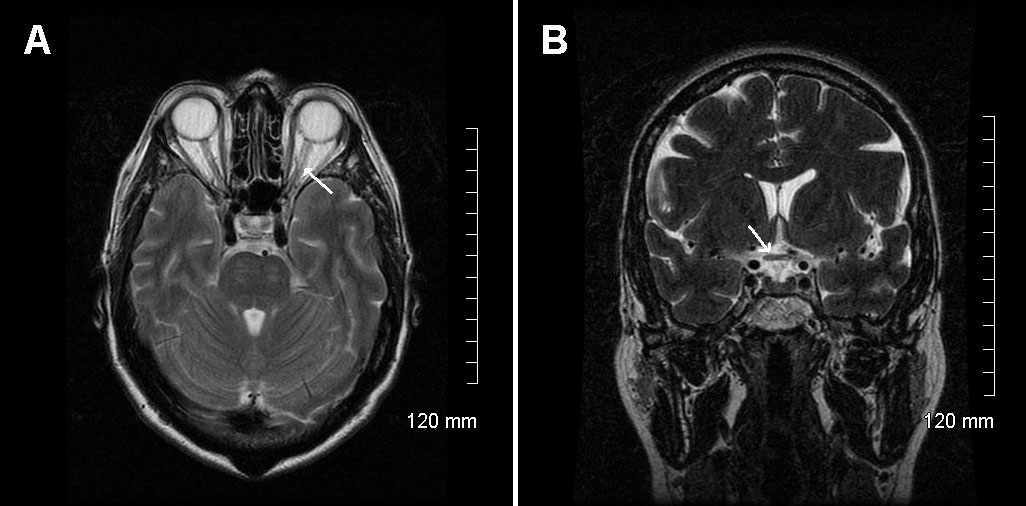

Figure 4. Patient's encephalic MRI. MRI of the optic nerve showed severe bilateral atrophy of the optic nerve from retina to the lateral

geniculate nucleus, seen on horizontal MRI section (A), including atrophy of the optic chiasma, seen on coronal MRI section (B).